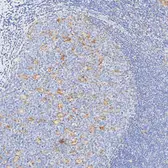

描述 Rabbit Monoclonal实验应用 IHC-P种属反应 HuSummary Highly recommended for IHC-P in human tissues. Autostainer protocol information available.